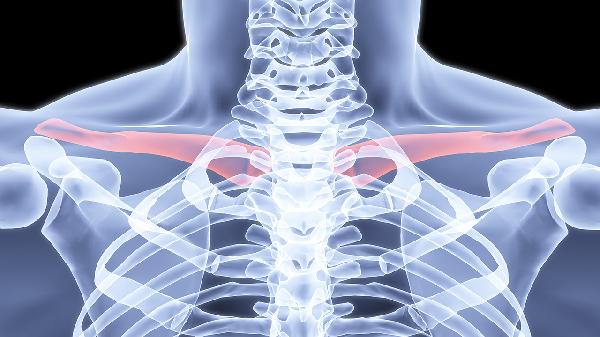

锁骨骨折多数情况下无需手术治疗。治疗方案选择主要取决于骨折类型、移位程度、患者年龄等因素,保守治疗方式包括八字绷带固定、锁骨带固定、限制活动、物理治疗及药物镇痛。

无移位或轻度移位的锁骨中段骨折通常选择保守治疗。这类骨折稳定性较好,通过外固定可达到自然愈合,愈合周期约6-8周。若为粉碎性骨折或伴有血管神经损伤,则需手术干预。

骨折端重叠小于2厘米或成角小于30度时优先考虑非手术治疗。严重移位可能导致畸形愈合影响肩关节功能,此时需手术复位内固定。儿童锁骨骨折因骨膜较厚,即使明显移位也多可保守治疗。

儿童和青少年锁骨骨折愈合能力强,90%以上可通过保守治疗恢复。中老年患者若合并骨质疏松,需评估骨折稳定性,非手术治疗期间需加强营养补充和防跌倒措施。